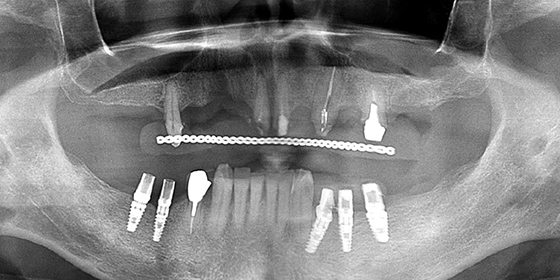

上顎前歯がグラグラして食事ができない患者様。上の骨質が悪く、下の歯も多数欠損しているケースを、上には骨造成をしてインプラント、下にはインプラントを行って噛み合わせを回復したケースです。

上の歯は支えを失いグラグラの状態です。下はほぼ前歯しか残っておらず、前歯が上の歯を突き上げるような噛み合わせになっています。

下顎のインプラントをコンピュータガイドサージェリーで行いました。下顎にインプラントを埋入した後は上顎にインプラントを埋入する準備を行います。

下顎に仮歯を装着する時点で上顎の噛み合わせの平面を揃える為、また上顎のインプラント埋入位置の骨の成熟を促す為、インプラントの埋入予定位置に存在する歯を先に抜歯して、上顎に全体的な仮歯を装着しておきます。

上顎の骨質が悪く足りないので、骨を増やす手術であるサイナスリフトを両側に行い、前歯にインプラントを埋入します。

サイナスリフトを行なった部位に骨ができたのを確認し、臼歯部分にコンピュータガイドサージェリーでインプラントを追加埋入します。